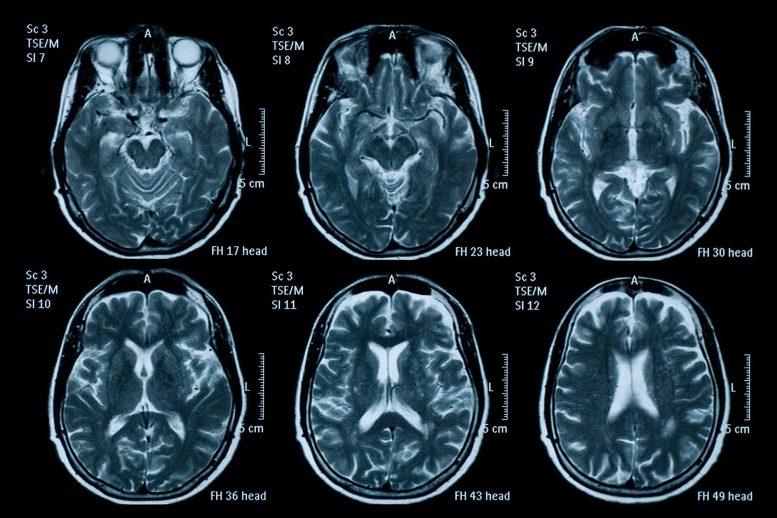

COVID-19患者的脑损害生物标记物高于阿尔茨海默病患者

一项新的研究发现,因COVID-19住院的患者的血液蛋白质水平在短期内高于被诊断为阿尔茨海默氏症的非COVID-19患者,而已知的血液蛋白质水平会随着神经损伤而上升。